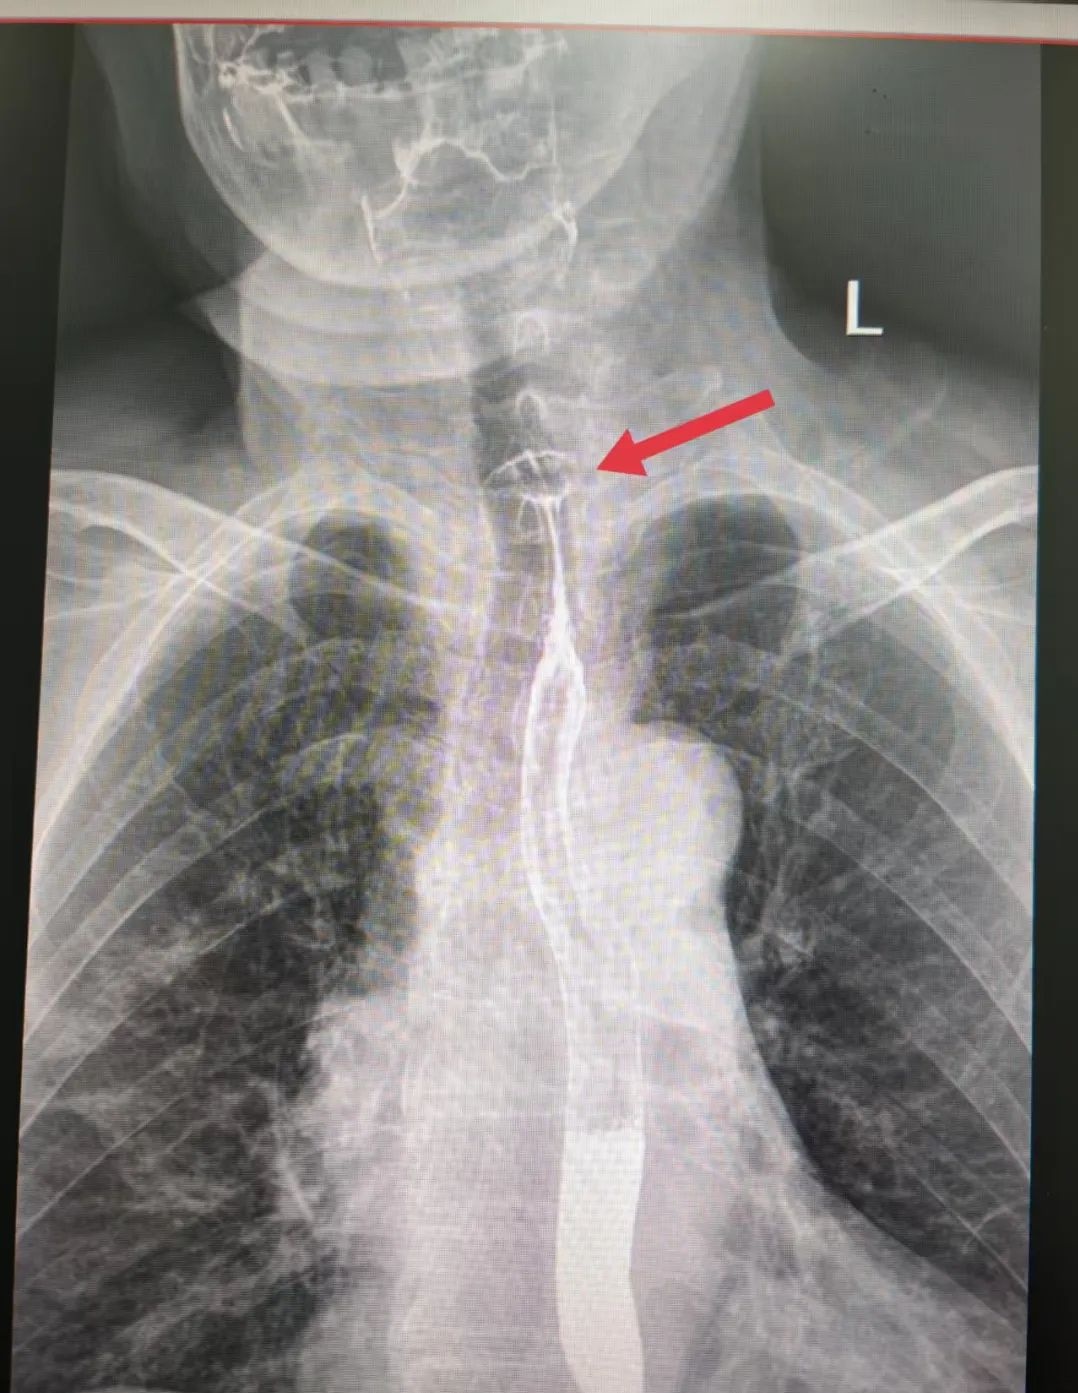

案例一:枣核卡喉 手术脱险

5月28日,陕西榆林75岁的高奶奶食用红枣粽时不慎吞下枣核,顿感咽喉不适、吞咽梗阻,紧急前往医院就诊。检查发现食管上段有异物,高奶奶被收治入院,经手术顺利脱险。

2.经过食管时可能卡在食管处或划伤食管,造成脓胸。因食管靠近主动脉,如果累及主动脉,可能引起大出血危及生命。